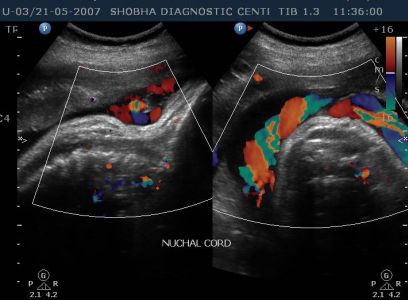

DOPPLER SONOGRAPHY / BIOPHYSICAL PROFILE

- It will also tell you if there is loop of umbilical cord Around baby’s neck.